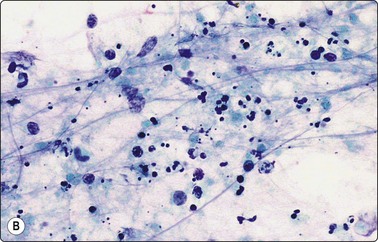

image image

Fig. 5.2 Small cell anaplastic carcinoma

Dispersed malignant cells with dense chromatin, irregular nuclear contour, nuclear molding, inconspicuous nucleoli and cytoplasm; note irregular cytoplasmic (B) and nuclear fragments in the background representing tumor necrosis (A and B) (MGG, HP).